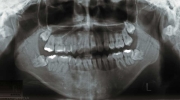

治療前後の比較